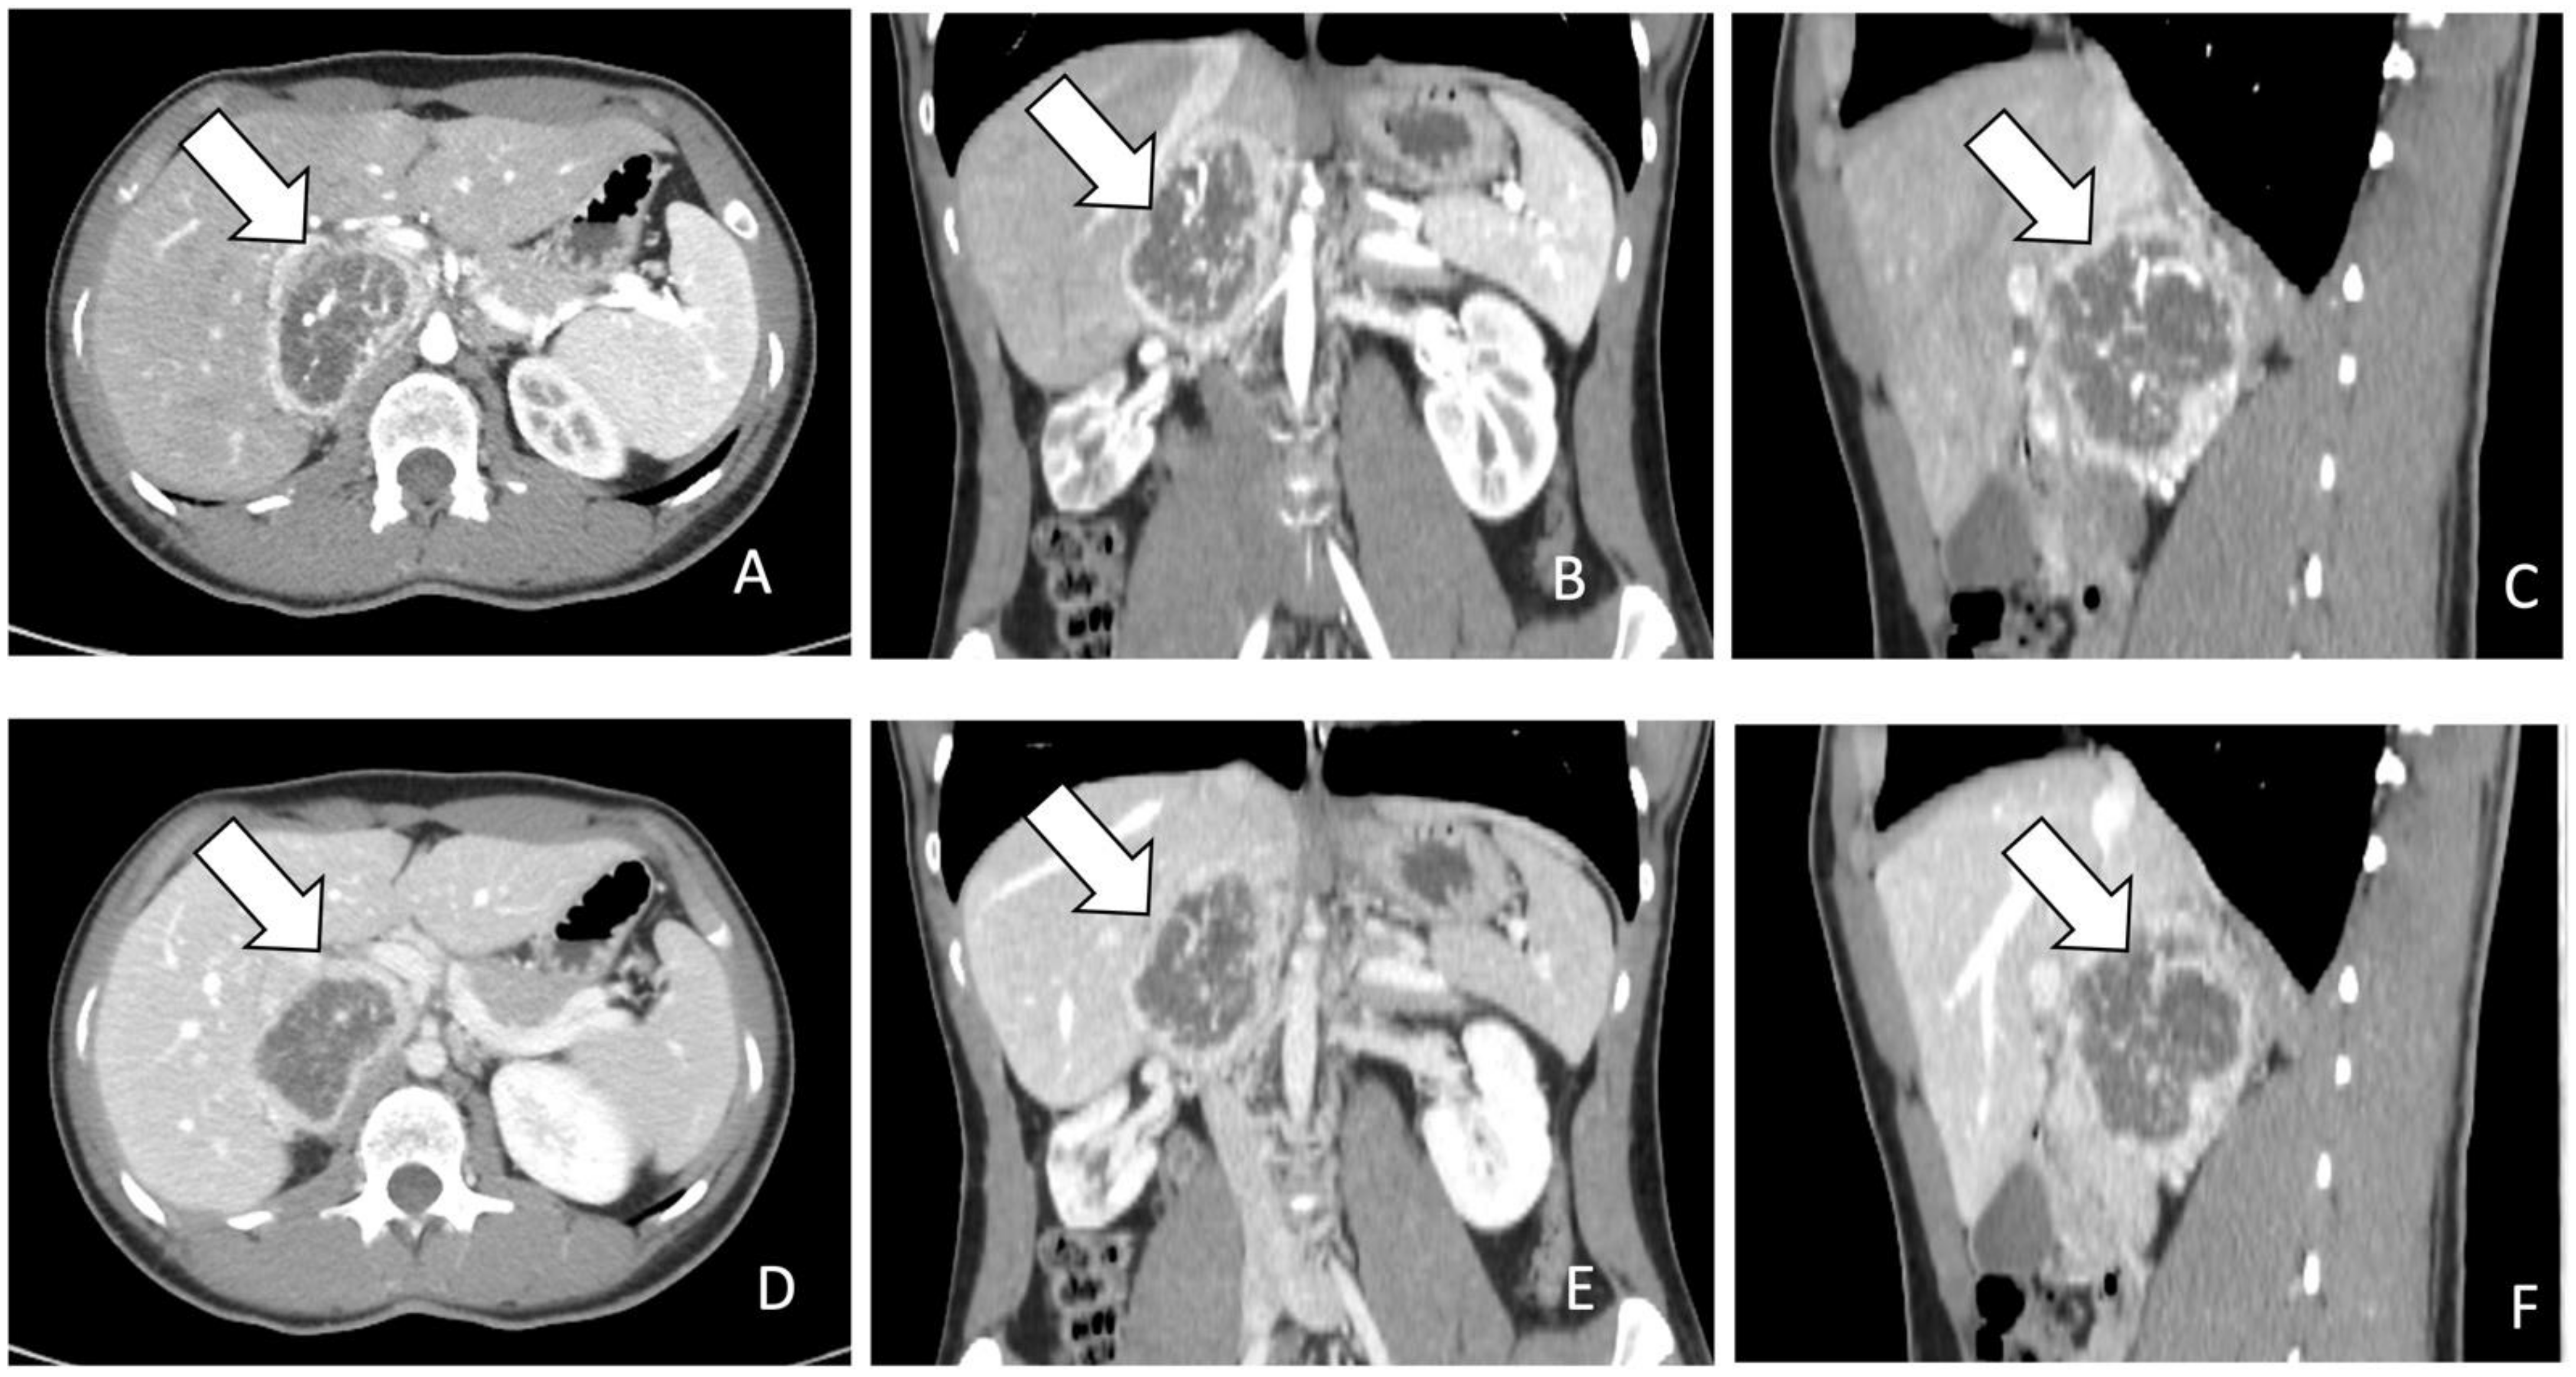

- Galatola, R.; Attanasio, L.; Romeo, V.; Mainolfi, C.; Klain, M.; Simeoli, C.; Modica, R.; Guadagno, E.; Aprea, G.; Basso, L.; et al. Characterization of Atypical Pheochromocytomas with Correlative MRI and Planar/Hybrid Radionuclide Imaging: A Preliminary Study. Appl. Sci. 2021, 11, 9666. [Google Scholar] [CrossRef]

- Galatola, R.; Romeo, V.; Simeoli, C.; Guadagno, E.; De Rosa, I.; Basso, L.; Mainolfi, C.; Klain, M.; Nicolai, E.; Colao, A.; et al. Characterization with hybrid imaging of cystic pheochromocytomas: Correlation with pathology. Quant. Imaging Med. Surg. 2021, 11, 862–869. [Google Scholar] [CrossRef] [PubMed]